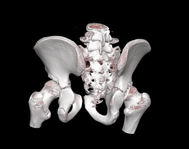

Preoperative planning is carried out through imaging studies, digital segmentation and 3D printing of the right hip (Figure 4), where the CAM-type morphology lesion can be evidenced. In the programmed operative room, under general anesthesia, in left lateral decubitus, an anterior approach to the hip is performed and dissection by planes up to the fascia, which is excised. Subsequently, an osteotomy of the greater trochanter is performed, release of the gluteus medius, the joint capsule is released, observing the femoral head with healthy articular cartilage; capsulotomy is performed and the Impingement test is performed under direct vision. Then, controlled hip dislocation is performed using a flexion and adduction maneuver, and resection of the anterolateral portion of the coxa magna is performed with an osteotome and shaver (DePuy-Synthes). Finally, hip reduction is performed and compliance is visualized under fluoroscopic vision in two planes, the greater trochanter is transposed and fixed with 2 6.5 mm cannulated screws (DePuy-Synthes), reduction compliance is visualized with fluoroscopic vision, and it is verified with direct visualization with a 3D model, suture is performed and the post-surgical cleaning with sterile dressings and gauze is performed, ending the procedure without complications. Radiological control is performed (Figure 5) and due to satisfactory postoperative evolution, medical discharge is decided after 24 hours. Radiographic control is performed at 6 months, where appropriate bone healing is evidenced (Figure 6).

Figure 4 3D printing of the right hip.

Three-dimensional printing is a technology that could be an excellent contribution in all the operative setting, planning, and the diagnosis, therefore it is very likely that we will continue to see an increase the work to generating publications in the coming years. In this particular case, the Three-dimensional model improves the direct visualization of the CAM lesion, and collaborate with the surgical team to realize the proper procedure.